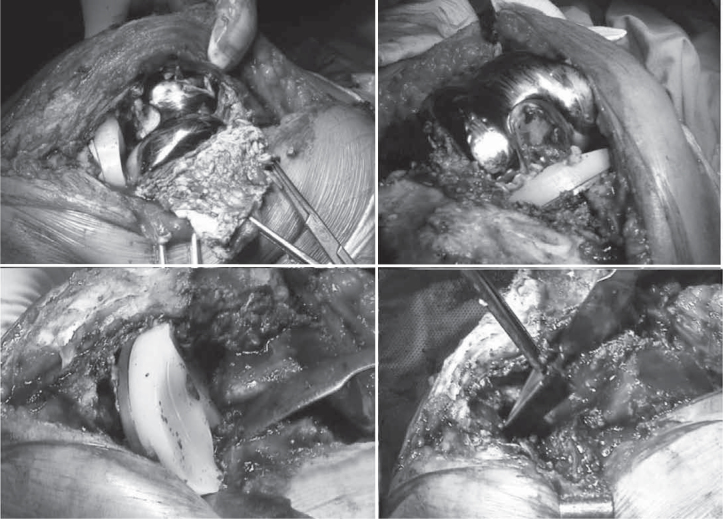

A knee radiograph was taken at the same time (Figure 1) and the patient was admitted to our clinic with a diagnosis of Mayo Clinic type IB tibial periprosthetic fracture(3). During surgical preparation and planning there was a more careful observation of the images, with detection of a tibial stem fracture at the tibial stem/baseplate transition (Figure 1). In view of these new data, the decision was made to conduct a review with deployment of total knee arthroplasty. In the perioperative period and after extraction of the tibial component the stem fracture was confirmed unequivocally (Figure 2). Both components and stems were replaced, and a tibial wedge (P.F.C. Sigma TC3 – Depuy Orthopaedics – Warsaw-IN) was included (Figure 3). The postoperative period elapsed without incidents.

Figure 2.

Total knee replacement with tibial stem fracture.

Figure 3.

Total knee replacement implanted.